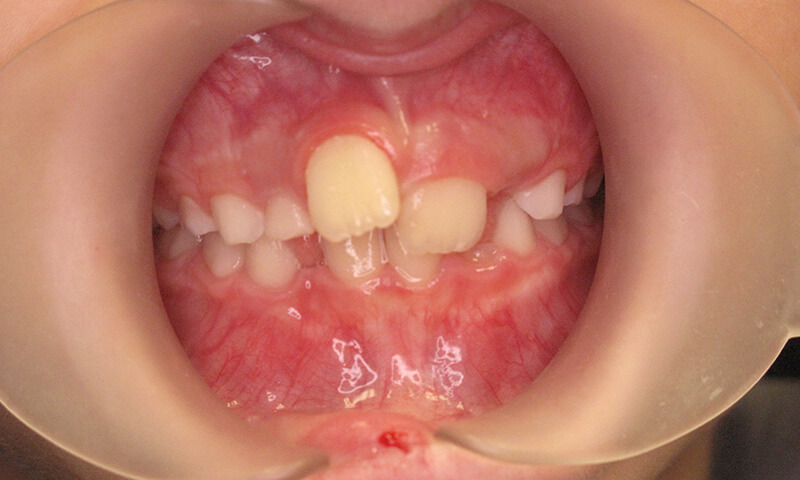

Before

After